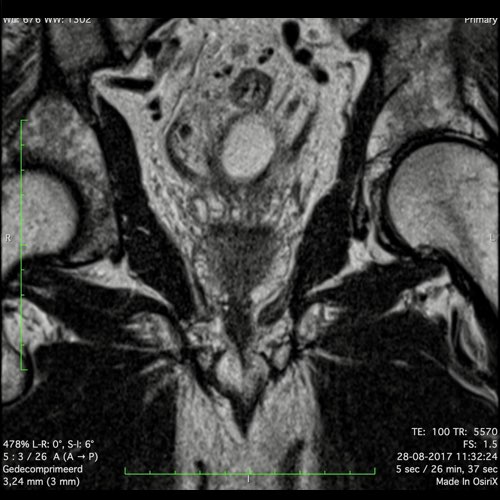

Hình ảnh

Các hình ảnh được cung cấp cho thấy ung thư biểu mô tế bào nhẫn với tình trạng dày lan tỏa thành trực tràng, hình ảnh bia bắn điển hình, và sự xâm lấn mỡ mạc treo trực tràng.